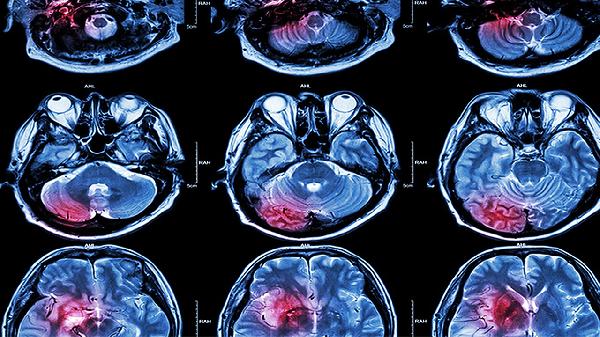

头颅CT能快速显示脑组织密度变化,典型脑水肿表现为低密度影伴脑沟回变浅。MRI对早期水肿更敏感,T2加权像可见高信号,扩散加权成像能区分细胞毒性水肿与血管源性水肿。这两种检查可明确水肿范围及是否合并出血、占位等病变。